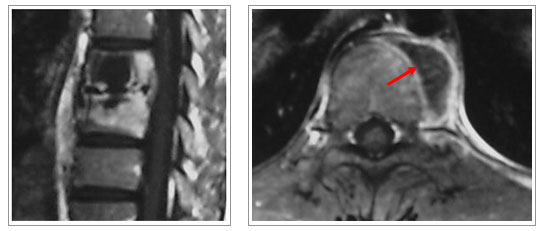

- 결핵성 척추염

폐결핵으로부터 혈행성으로 척추골결핵을 일으키는 질환이며 추체가

파괴되는 증상부터 시작됩니다. 추체의 파괴가 진행되면 환부에 심한 통증이 오고 척추경직,자세이상

등의 증상이 나타납니다. 치료는 안정을 취하고 항결핵제를 사용하거나 추체고정술 등의 수술적

요법이 필요할 수도 있습니다. |

1)

진단

| |

- 단순방사선

- 골스캔

- 자기공명영상

- 결핵반응검사 |

2)

치료

| |

- 항결핵제 + 외고정(보조기)

- 수술적 치료 ; 병소절제술 및 자가 골이식 및 내고정술 |